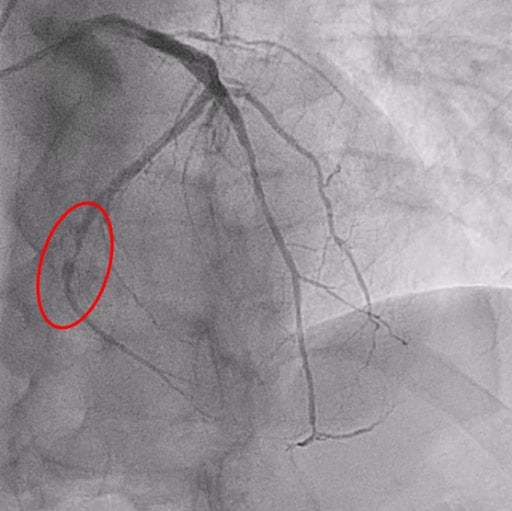

Figure 4: Final result

If the outcome is satisfactory, with no flow-limiting dissections, the procedure can be considered complete. However, if there is flow reduction and/or a significant dissection (type C or higher), vessel recoil > 30 % or fractional flow reserve ≤ 0.80, bailout stenting is recommended.